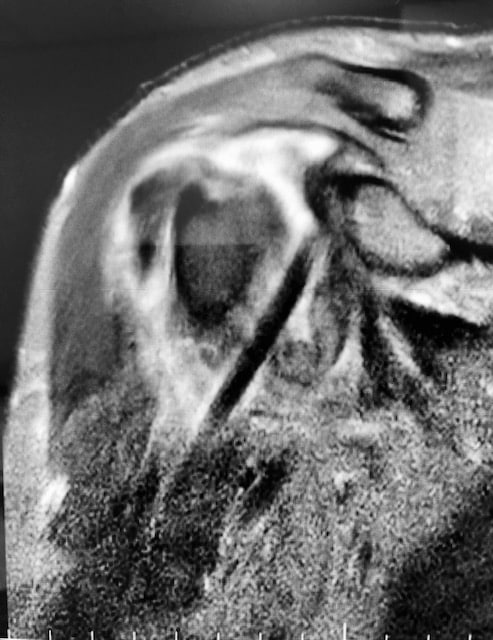

Rupture de la coiffe des rotateurs

Usure de la coiffe des rotateurs

La coiffe des rotateurs est le nom d’un ensemble de tendons (sous scapulaire, sus-épineux, sous-épineux et petit-rond) situés sur la tête de l’humérus et dont la fonction est essentielle dans la mécanique de l’épaule. La coiffe peut être le siège d’une lésion, d’une déchirure, soit progressive, appelée rupture dégénérative (usure), soit plus rarement liée à un traumatisme (rupture traumatique). Elle concerne soit un seul tendon, fréquemment le sus-épineux, soit deux ou trois tendons.

Le diagnostic repose principalement sur l’IRM et la radiographie.